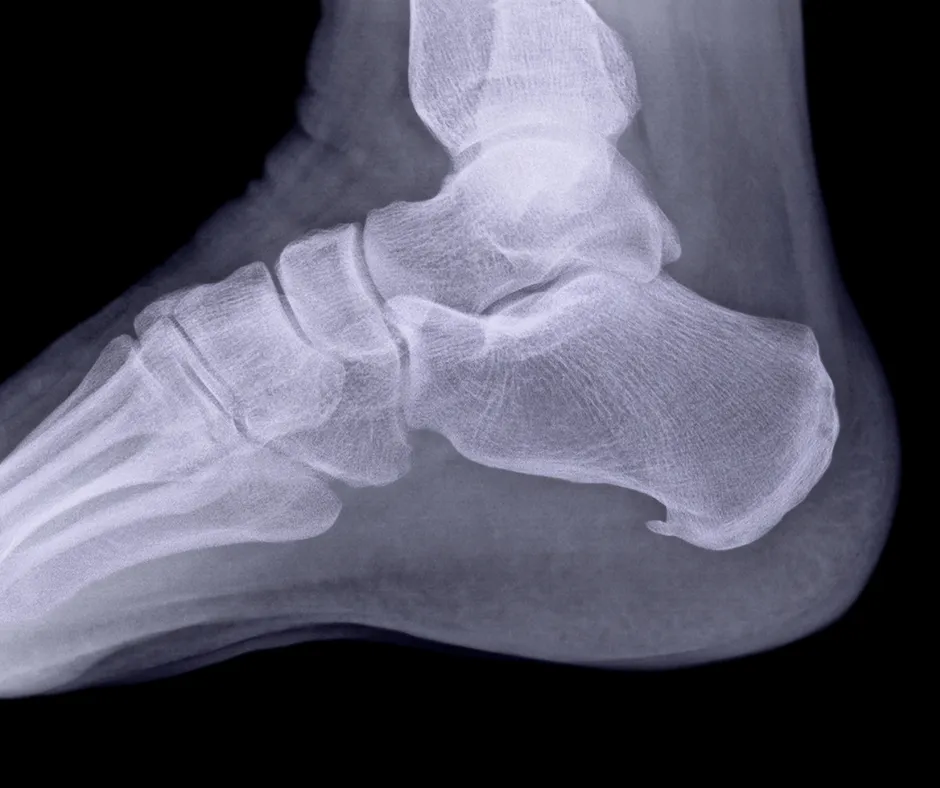

Ein Fersensporn ist eine knöcherne Auswucherung an der Ferse, die durch wiederholte Spannung der Plantarfaszie verursacht wird. Die Plantarfaszie ist ein Bandgewebe, das den Fussbogen stützt. Die übermässige Belastung führt zur Bildung des Fersensporns, der wiederum Schmerzen und Entzündungen verursachen kann.